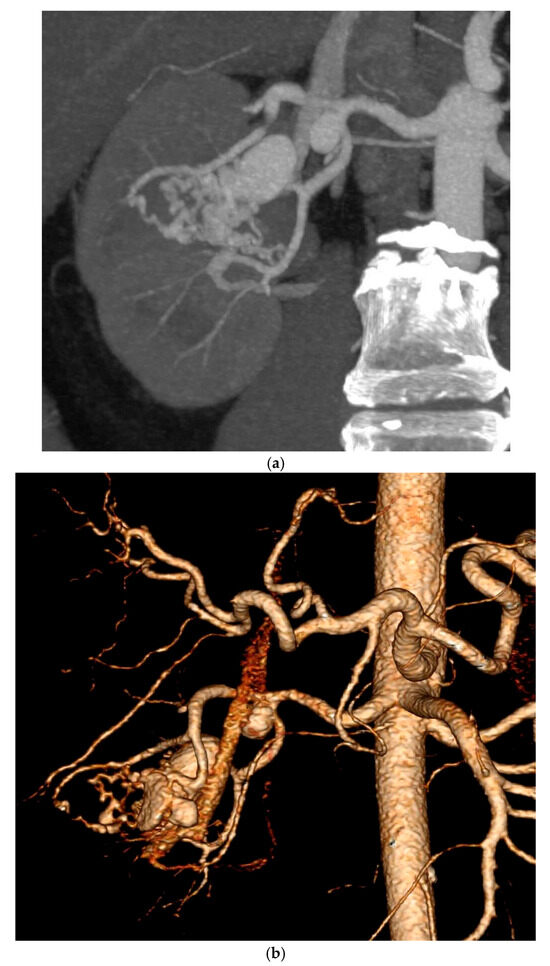

Resolution of Proteinuria After Renal AVM Embolization with Combined ACEi and SGLT2i Therapy: A Case Report

by Ana Mijušković, Jelena Pavlović, Vladimir Cvetić, Borivoje Lukić, Ana Bontić, Selena Gajić, Kristina Filić, Ivana Mrđa, Aleksandar Sič, Nikola Trnić and Marko Baralić

Kidney Dial. 2025, 5(4), 54; https://doi.org/10.3390/kidneydial5040054 - 13 Nov 2025

Background: Renal arteriovenous malformations (rAVMs) are rare vascular anomalies that may lead to hematuria, anemia, or acute kidney injury (AKI). Although endovascular embolization is the treatment of choice, post-procedural complications such as new-onset proteinuria may occur and require long-term management. Case Presentation: A [...] Read more.

Background: Renal arteriovenous malformations (rAVMs) are rare vascular anomalies that may lead to hematuria, anemia, or acute kidney injury (AKI). Although endovascular embolization is the treatment of choice, post-procedural complications such as new-onset proteinuria may occur and require long-term management. Case Presentation: A 56-year-old man with recurrent gross hematuria and elevated serum creatinine (128 μmol/L) was diagnosed with a right rAVM and underwent successful selective embolization. Despite recovery of renal function, follow-up revealed new-onset proteinuria (2.2 g/24 h). Results: Introduction of an angiotensin-converting enzyme inhibitor (ACEi) resulted in partial improvement of proteinuria, while subsequent addition of a sodium–glucose cotransporter-2 inhibitor (SGLT2i) achieved almost complete resolution of proteinuria (0.33 g/24 h) and stable renal function (serum creatinine 93 μmol/L) after 12 months. Conclusions: This case highlights the occurrence of post-embolization proteinuria and illustrates the synergistic renoprotective effect of combined ACEi and SGLT2i therapy in a non-diabetic patient with vascular kidney disease. Full article

Show Figures

Graphical abstract